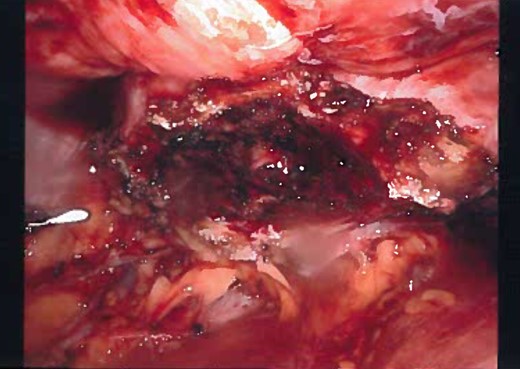

Inflamed and necrotic appearance of the urachal cyst with multiple pus filled cavities.

Gross appearance of the urachal cyst resembled an inflammatory and necrotic appearance with multiple cystic cavities (Figs 3 and 7). On pathology, tentative diagnosis of the specimen was confirmed as an urachal cyst. The appearance of an ulcerated cyst wall noted with marked fibrosis, acute and chronic inflammation with focal abscess, foreign body giant cells, and fibrous adhesions, consistent with history of infected urachal cyst and no evidence of malignancy. Intra-operative culture of urachal cyst provided contents positive for Escherichia coli, and negative for fungal material. The patient had an uneventful post-operative course. We followed up the patient in 2 weeks and again in 3 months in the outpatient clinic. During the follow-up, patient reported that removal of the cyst helped her abdominal pain, urinary tract symptoms have completely resolved and constipation was improve pertinently.